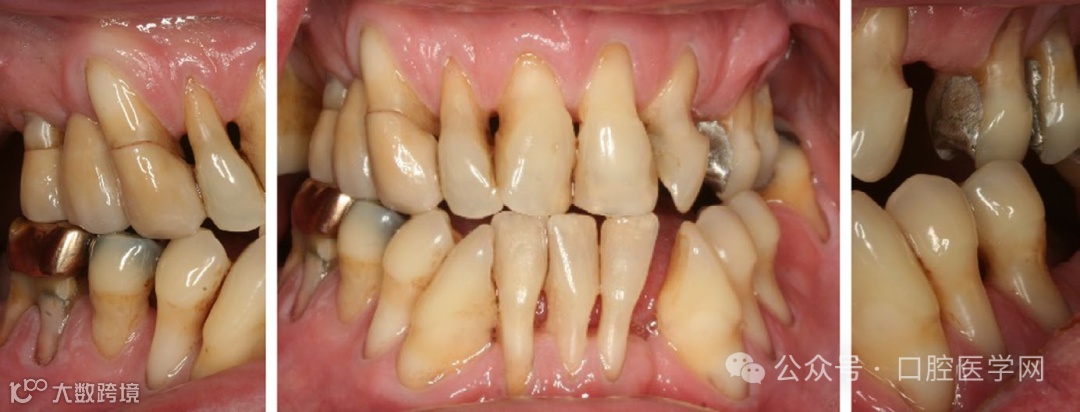

牙周治疗可能包括不同的手术、骨增量和支持性牙周治疗。支持性牙周治疗涉及严格的随访、频繁的洁治和根面平整,最重要的是口腔卫生教育和指导。牙周治疗后适当的支持性牙周治疗在文献中有显著的成功案例,并且似乎取决于患者的依从性(图1)。如果患者遵循医嘱配合良好,受损牙齿的生存几率将会提高。经适当治疗和定期维护的牙周受损牙齿的存活率范围在92%-93%之间。此外,即使是在被诊断为C级牙周病(以前被称为侵袭性牙周炎)的患者中,被认为无希望保留和存疑的牙齿的存活率也分别达到60%-88%。因此,不应仅仅因为拔牙看似是较简单的治疗方案就优先考虑拔牙,而应优先采用牙周治疗结合适当的支持性牙周治疗来保留牙周受损牙齿。若这种治疗不成功且必须拔除牙齿,仍然可以选择种植体作为备选方案,因为作为备份治疗手段,种植体10年的存活率可达82%-94%。

图1

一位患者在经过支持性牙周治疗后,其牙周状况已得到稳定,尽管牙周组织明显减少。目前,患者的牙齿无松动现象,且不存在牙周袋或活动性牙周病灶。